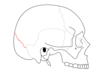

Identify the coloured parts

Identify the labels

- Frontal bone

- Parietal bone

- Occipital bone

- Temporal bone

- Sphenoid bone

- Zygomatic bone

- Mandible

- Maxilla

- Vomer (inf. nasal concha)

- Nasal bone

- Lacrimal bone

- Ethmoid bone